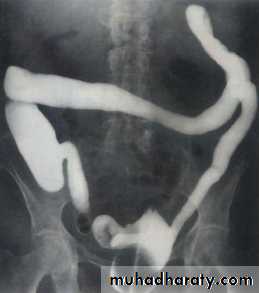

Volvulus

Frequently seen in sigmoid and less often in cecumThe twisted loop becomes greatly distended and proximal bowel dilatation is noted

The diagnosis can be made from plain film

Ba enema will show smooth tapered narrowing with marked dilatation of proximal bowel